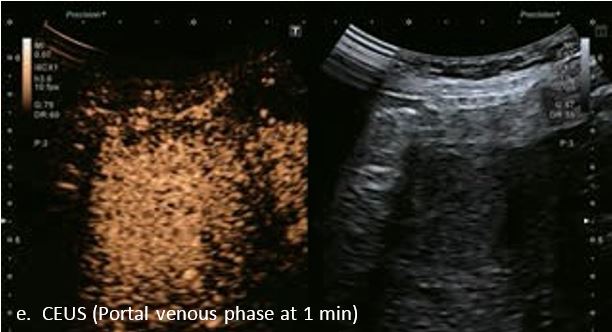

LI-RADS 5 ГЦК

У 63-річної жінки з алкогольним цирозом печінки виявлено ураження печінки розміром 3 см. Межа ізоехогенного ураження та його гіпоехогенний ореол може бути чітко відображений на сірошкальному зображенні. За допомогою кольорового доплера можна виявити внутрішньопухлинну судинну структуру. Багата судинна структура може бути окреслена за допомогою SMI, та можуть бути показані викривлені судини, що свідчить про злоякісне ураження. Після ін'єкції контрасту, в артеріальній фазі, ураження демонструє гомогенне гіперпосилення, пов'язане з підживлюючими судинами. Вимивання не спостерігається на 1 хвилині і на 2 хвилині. У відстроченій фазі на 3,5 хвилині можна спостерігати помірне вимивання. Вимивання повільно прогресує і стає більш чітким на 5 хвилині. Пізнє (≥ 60 сек) і помірне вимивання є однією з основних ознак LI-RADS 5 і є дуже важливим для диференціації від LI-RADS M, який показує раннє (<60 сек) і/або виражене вимивання. В результаті ураження класифікується як CEUS LI-RADS 5. Класифікація CEUS LI-RADS відповідає LI-RADS на КТ.

Малюнок 9